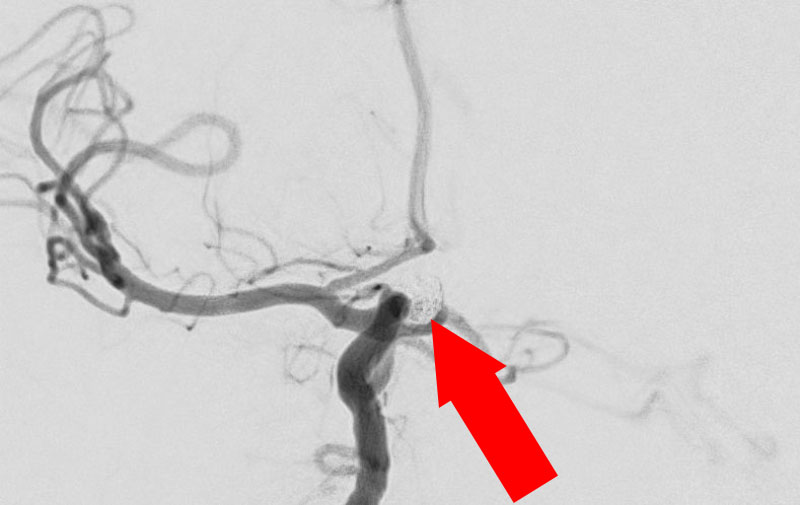

No.1631 手術中